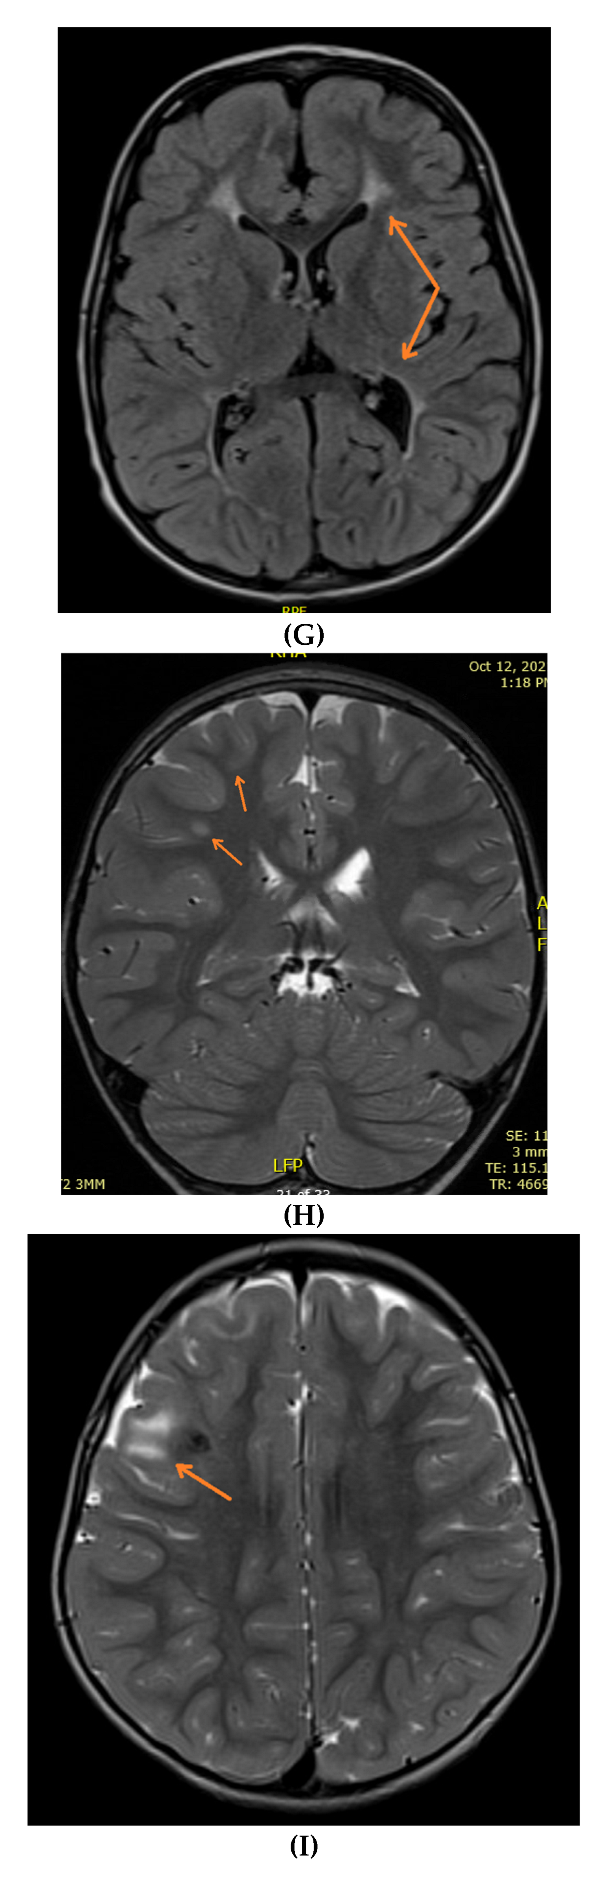

Brain MRIs showing the following (A): signs of hypoxia (T2 axial) with diffuse periventricular leukomalacia, enlarged ventricles and global atrophy (arrows); (B): delayed myelination in a 2-year-old child with diffuse hyperintense white matter compared to gray matter and brainstem (T2 axial); (C): dysgenesis of corpus callosum affecting its rostrum, genu, trunk and splenium (T1 sagittal) (arrows); (D): diffuse brain atrophy with enlarged ventricles (T1 axial); (E): severe ventricular dilatation (T2 axial) in a child with congenital muscular dystrophy; (F): intraventricular hemorrhage III (arrows) and hydrocephalus (T1 axial); (G): periventricular leukomalacia (T2 axial) (arrows); (H): non-specific white matter changes right precentral (T2 coronal) (arrows); (I): right frontal cortical tuber in a child diagnosed with tuberous sclerosis (T2 axial) (arrows); (J): PVL and frontal pachygyria (T2 axial) (arrows).